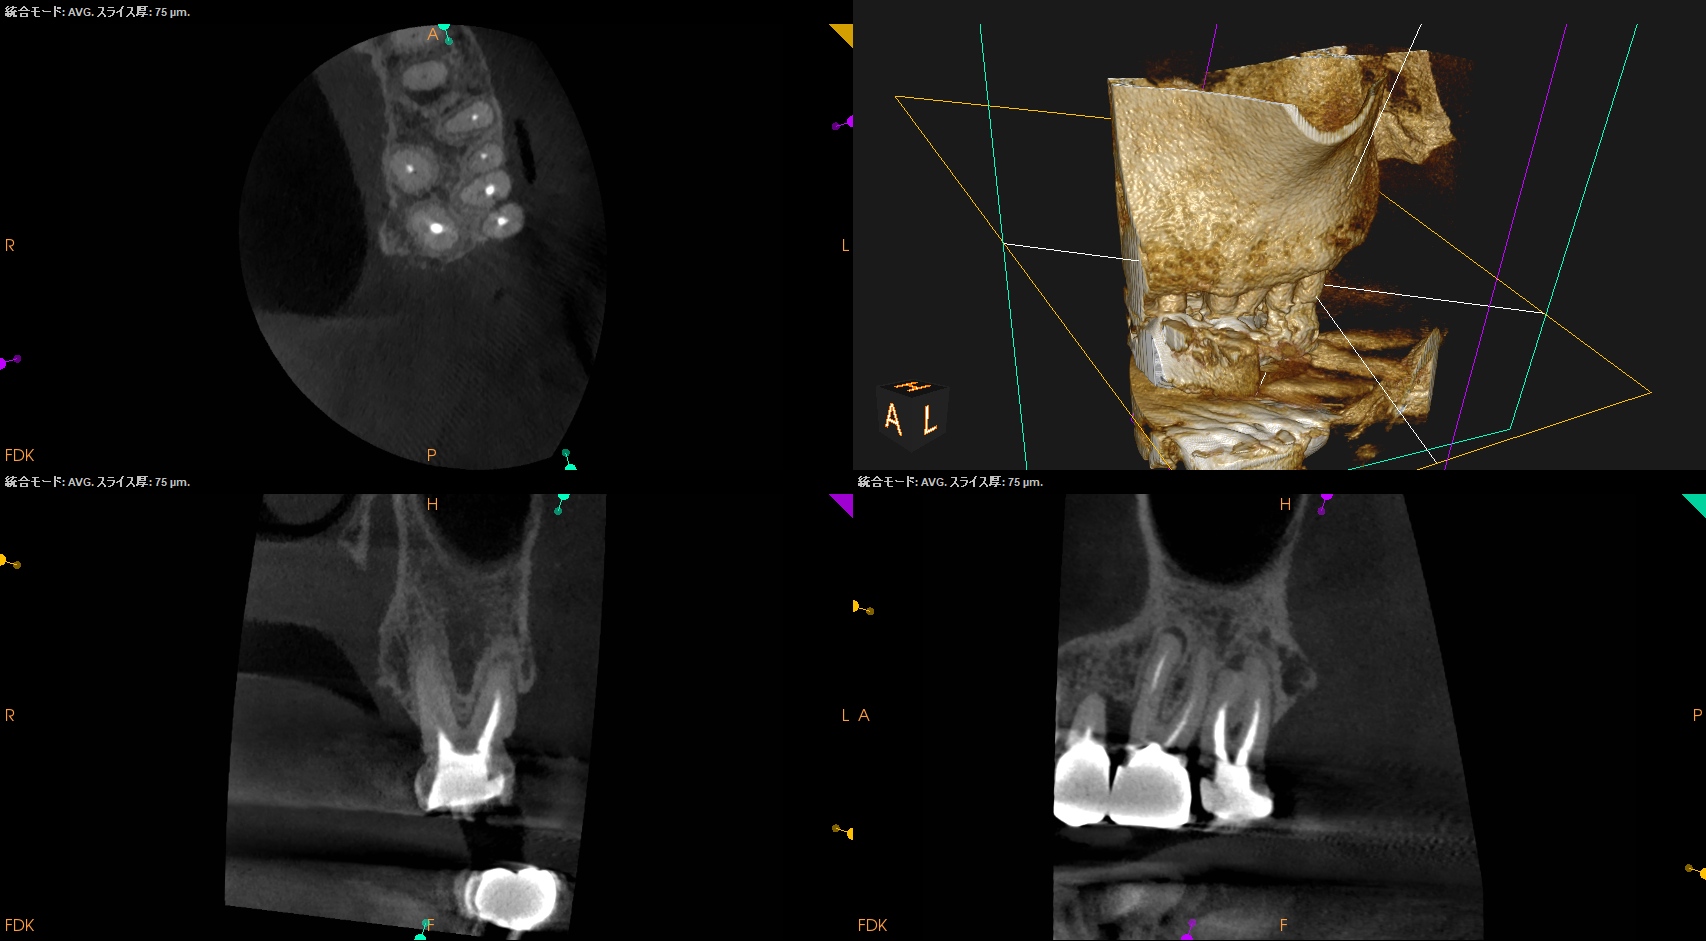

術後にPA, CBCTを撮影した。

MB, MB2

MB2は見つけられなかったが、MB2はMB1に合流していることがわかる絵である。

DB

P

問題はないと思われる。